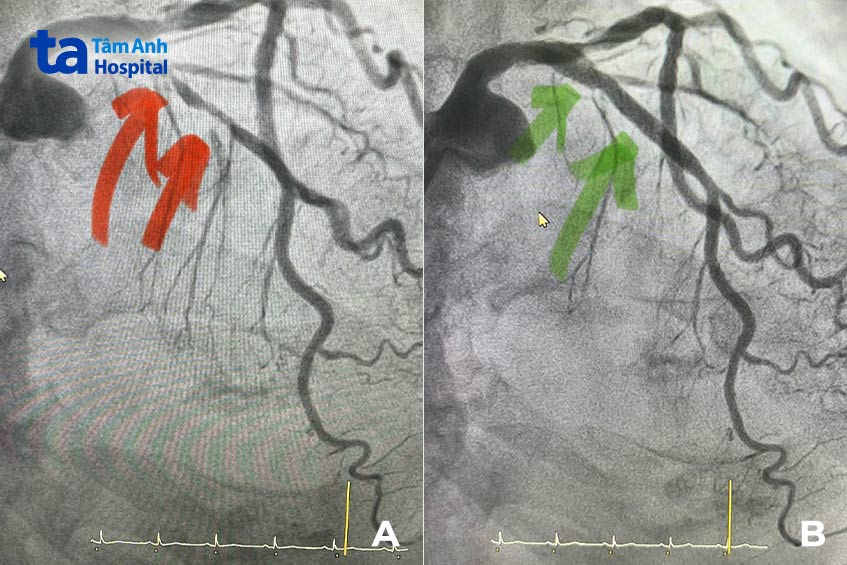

BS.CKII Huỳnh Ngọc Long, Giám đốc Trung tâm Can thiệp Mạch, Trung tâm Tim mạch, cho biết ông Hoàng không bị đau thắt ngực – triệu chứng điển hình nhất của bệnh mạch vành, nhồi máu cơ tim. Tuy nhiên, kết quả đo điện tâm đồ ghi nhận tình trạng thiếu máu cơ tim nghiêm trọng. Bác sĩ chỉ định bệnh nhân chụp mạch vành, xác định động mạch liên thất trước hẹp nghẽn nặng (90 – 95%), xơ vữa rải rác. “Đây là tình trạng dọa nhồi máu cơ tim rất nguy cấp, có thể khiến tim ngưng đập bất cứ lúc nào”, bác sĩ Long nhận định.

Vì bệnh nhân suy thận nặng, bác sĩ cố gắng không dùng quá nhiều thuốc cản quang. Đồng thời, ê kíp sử dụng kỹ thuật siêu âm trong lòng mạch vành – IVUS để ước lượng lòng mạch hẹp, xác định chính xác vị trí hẹp, từ đó chọn bóng và stent phù hợp. Điều này giúp rút ngắn tối đa thời gian can thiệp, giảm nguy cơ rủi ro trong và sau can thiệp xuống mức thấp nhất.

Sau 35 phút, ca thủ thuật kết thúc với 1 stent kích thước 3.5×48 mm và nong bóng 5.0 mm, phủ toàn bộ đoạn mạch hẹp nghẽn từ thân chung mạch vành trái đến đoạn gần động mạch liên thất trước. Tổng lượng cản quang sử dụng chỉ 26 ml (một ca đặt stent thông thường dùng khoảng 50 – 100 ml cản quang).